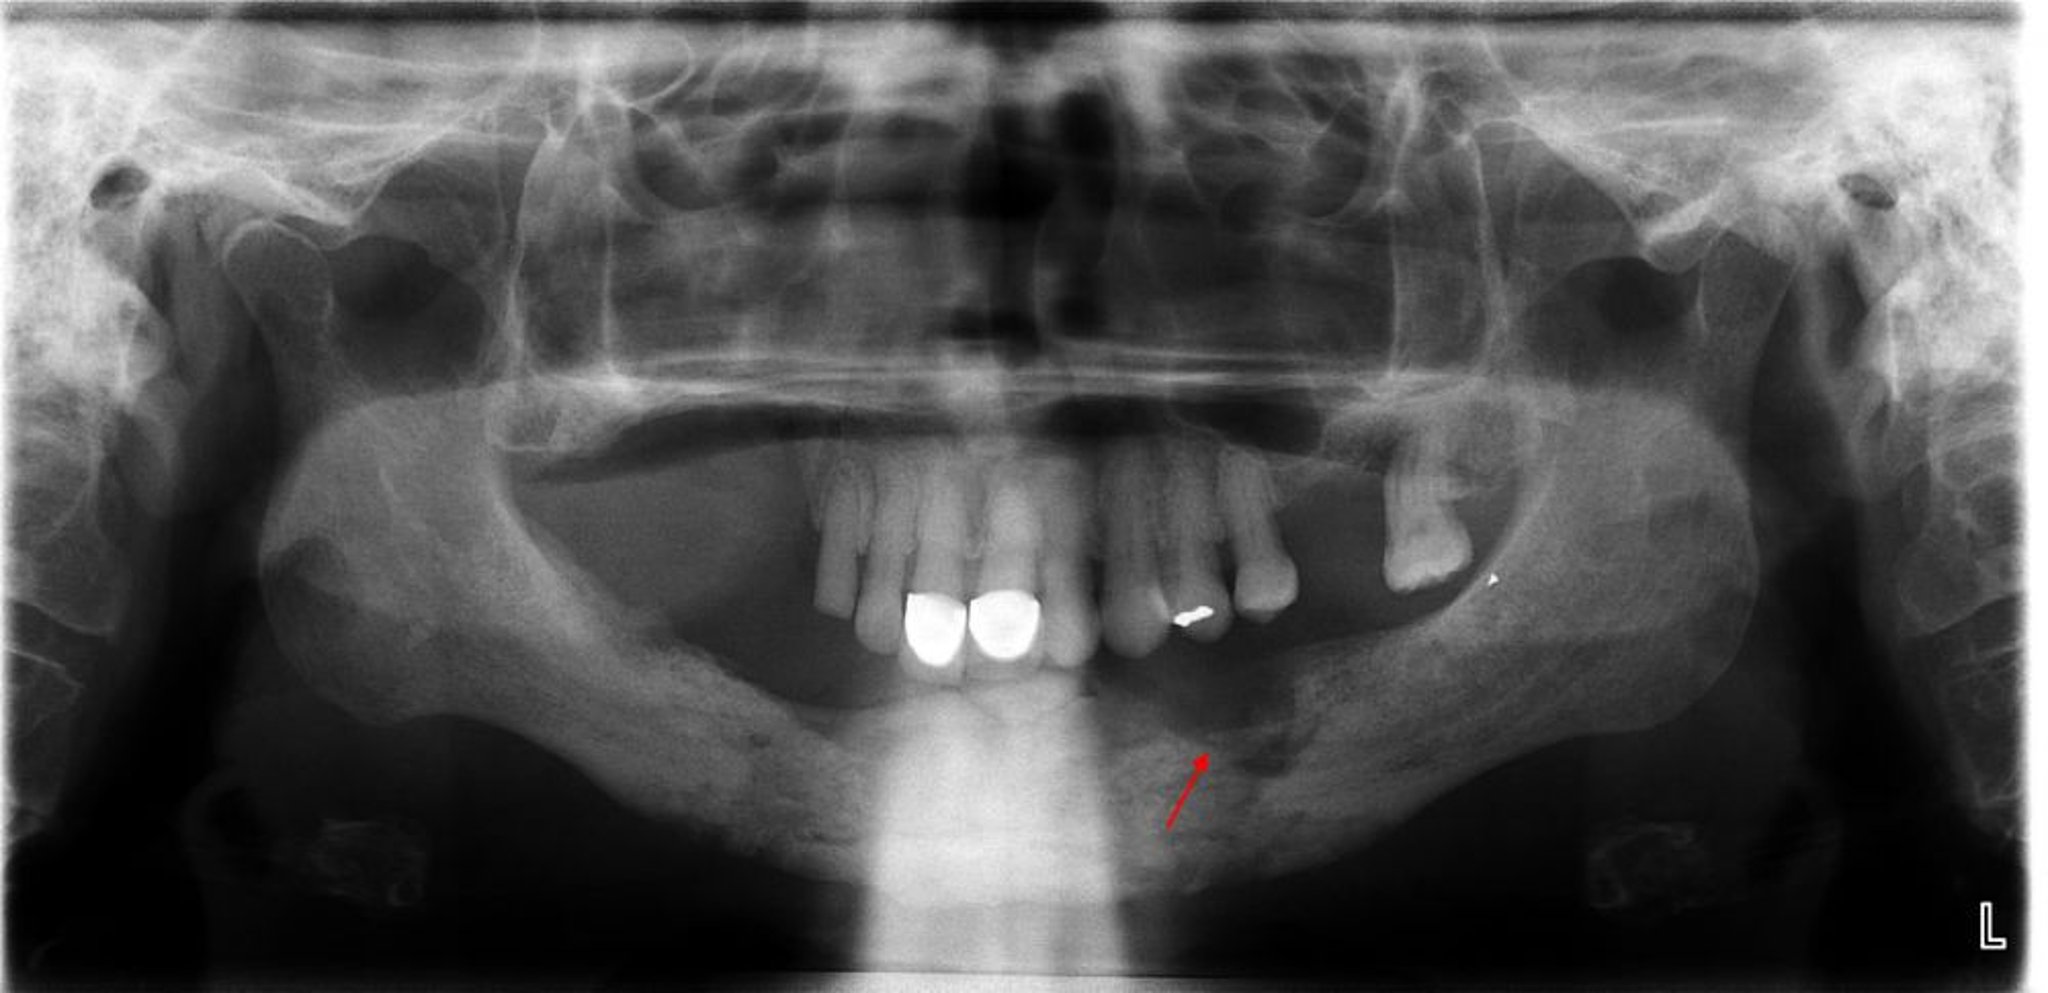

Esta radiografía revela osteomielitis con un secuestro evidente (hueso no viable) en el cuadrante mandibular izquierdo (flecha).

Image courtesy of Byron (Pete) Benson, DDS, MS, Texas A&M University Baylor College of Dentistry.